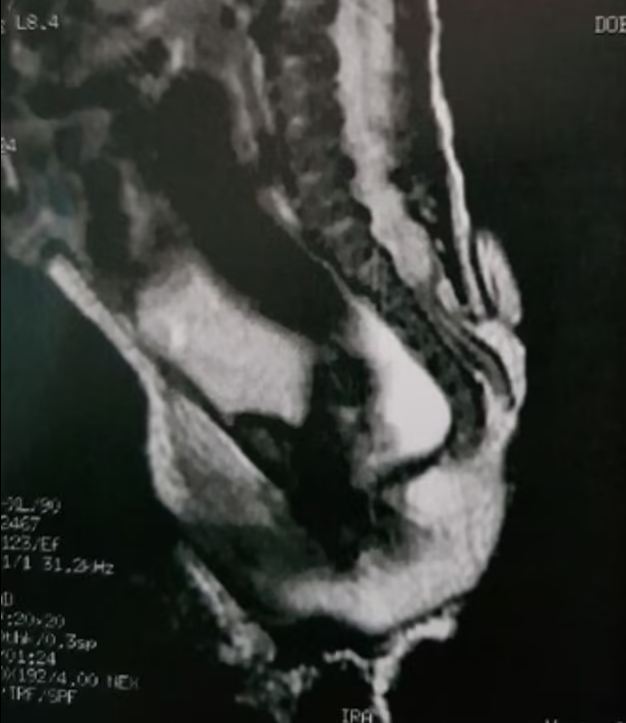

ونشرت مجلة Journal of Pediatric Surgery Case Reports، صورا لا تصدق قبل العملية وبعدها، تُظهر الفتاة بعد ثلاث سنوات من العملية التي غيرت حياتها.

وتمكن الجراحون من إزالة الذيل وإغلاق الفجوة في العمود الفقري. وكشف الأطباء من GRENDAAC، وهو مستشفى للأطفال في ساو باولو، إن الذيل انتشر من المنطقة القَطنية العجزية، المنطقة التي تربط العمود الفقري بالحوض.

وشخص الفريق هذه الأنسجة الزائدة على أنها "ذيل بشري زائف" (pseudo-tail)، وهو نمو يشبه الذيل ولكنه ناتج عن مشاكل العمود الفقري أو الأورام.

ودرس باحثون من مركز أبحاث الجنين والمشيمة في أوهايو الحالة إلى جانب الأطباء البرازيليين. وكتبوا: "الزوائد الذيلية البشرية هي آفات نادرة تفرض وصمة عار كبيرة على حامليها وأولياء أمورهم. وترتبط الزوائد الذيلية الجنينية بخلل العمود الفقري (السنسنة المشقوقة)، وبالتالي فإن وجودها يتطلب فحصا دقيقا لعيوب الحبل الشوكي الكامنة. إن تحديد العديد من الحالات الشاذة المرتبطة المحتملة أمر بالغ الأهمية لتخطيط العلاج الصحيح وتقديم مشورة جيدة".